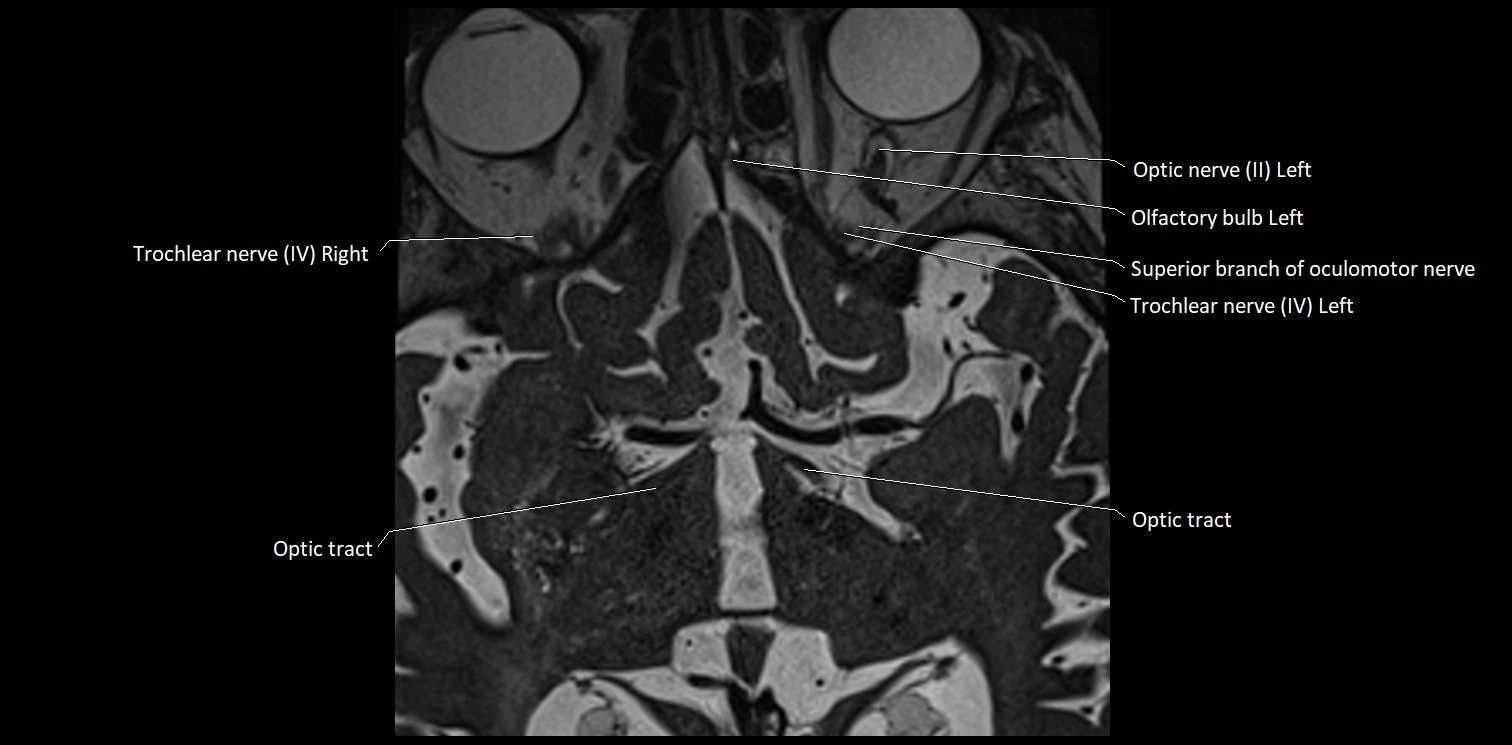

MRI Appearance

• The abducens nerve is a small, thin, linear structure

• Best visualized on high-resolution T2-weighted 3D MRI sequences (e.g., FIESTA or CISS)

• Seen as a hypointense (dark) line running from the brainstem at the pontomedullary junction, traversing the prepontine cistern, and entering Dorello’s canal under the petrosphenoidal ligament, then into the cavernous sinus, and finally the orbit

• May be challenging to visualize in standard MRI due to its small size

• Pathology may be inferred by absence, displacement, or enhancement of the nerve

MRI images

image